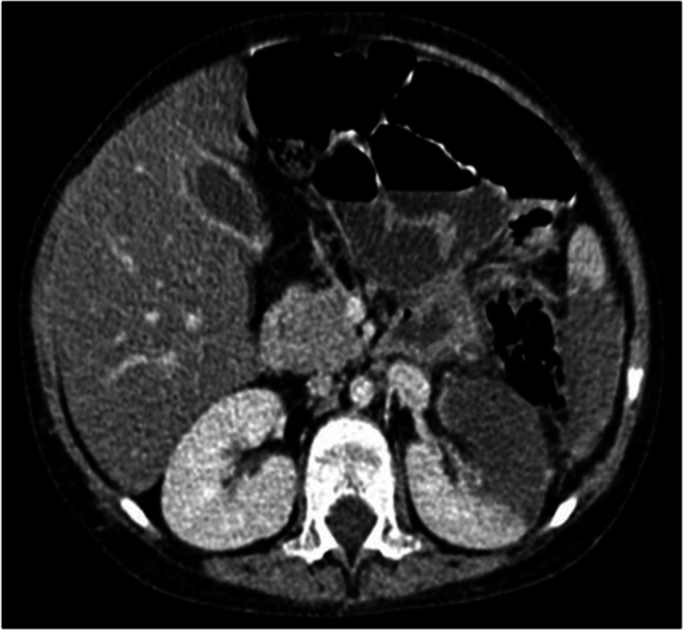

Fig. 1.

CT scan showed colonic mural thickening in the splenic flexure, infarct formation in the kidney and spleen which were suggestive of IA on the 8th day.